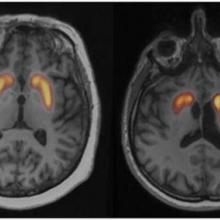

- Le Data Challenge Dat-Hub : dans le domaine de la neurologie, la Société Française de Médecine Nucléaire organise un challenge consacré aux syndrômes parkinsoniens. Les participants auront pour mission de développer un algorithme contribuant au diagnostic de ces syndrômes aux formes multiples. Des données d’imagerie cérébrale, appelées DatScan, de plusieurs milliers de patients seront mises à disposition pour le challenge.